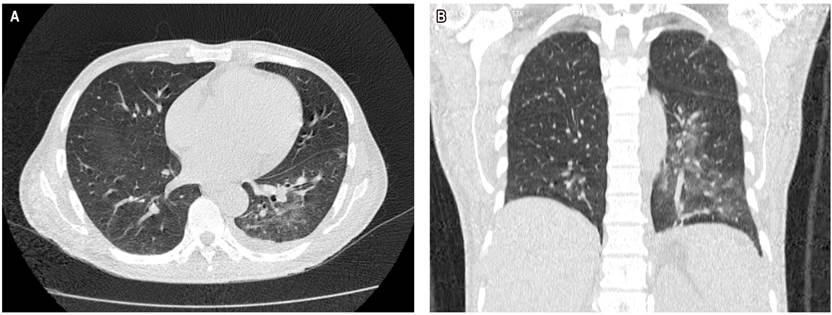

En la tomografía axial computarizada (TAC) de tórax se evidenciaba consolidación alveolar con infiltración en ambas bases pulmonares en vidrio deslustrado y engrosamiento septal (Figura 2). En la TAC de abdomen y pelvis se evidenció una masa tumoral de aspecto infiltrativo de aparente origen gástrico de aproximadamente de 25 x 25 x17 cm con extensa destrucción de la pared y la mucosa, con infiltración endoluminal y crecimiento extragástrico, metástasis hepática (hepatomegalia con dos lesiones hipoatenuantes de aspecto secundario, que miden 72 x 41 mm y 86 x 75 mm respectivamente en los segmentos hepáticos IV y V, e infiltración del hilio hepático, lo que produce dilatación de la vía biliar intrahepática) infiltración del bazo, del páncreas, de la raíz mesentérica, del omento mayor, del colon transverso, de las asas intestinales delgadas, de la porta y de los ganglios linfáticos periaórticos y pericavales, el mayor mide 13 mm (Figuras 3 y 4).

Figura 2 TAC de tórax. A. Corte transversal en el que se observa consolidación alveolar, con infiltración en ambas bases pulmonares en vidrio deslustrado. B. Corte coronal en el que se observa consolidación alveolar, con infiltración en base pulmonar izquierda en vidrio deslustrado.